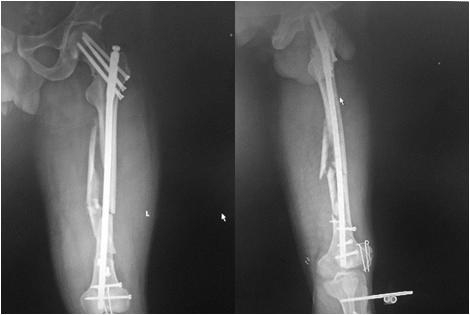

除孔镜技术外,传统骨科手术也越来越讲求小切口、少剥离、早康复的治疗原则。不再一味地要求解剖复位、而是更注重生物学功能。如图所示、微创手术在术中对周围软组织的干扰更小、术后相关后遗症明显降低。

这是我们对股骨多段粉碎性骨折采用小切口复位微创髓内钉固定手术,朋友们包括患者和家属当时看了这个术后复片之后对我们的手术技术是不认可的,对术后功能的恢复也是质疑的,最后愤愤然地出院了。

其实不然,微创理念要求我们不去破坏骨骼再生修复的内环境,这就不能像传统手术一样将每一块碎骨都拼回原位、修复如新。我们不再以此为目的大肆破坏周围结构、为了追求片子上的完美(我们称之为解剖复位)而导致患者部分功能破坏、终身肢体残障。

该患者及家属在1年后特地带着锦旗和鲜花来感谢我们,最让我们欣慰的不是这些,而是看到患者肢体良好的功能恢复,骨折的完全愈合。